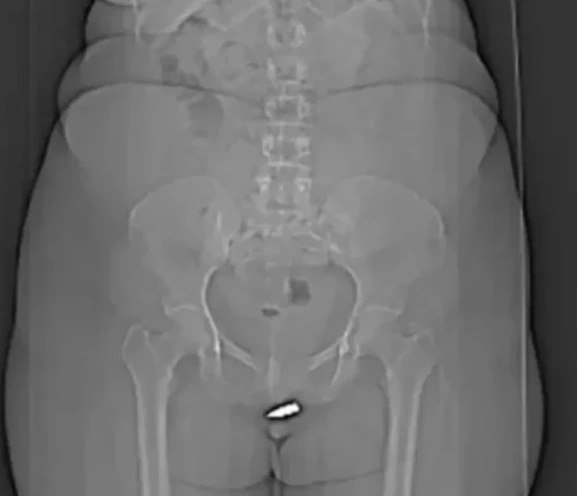

Согласно имеющейся информации, инцидент произошел в гостиничном номере. Двадцатичетырехлетняя потерпевшая утверждает, что во время ее пребывания в комнате кто-то произвел выстрел, пробив потолок, и пуля попала непосредственно в область ее гениталий. Напуганная случившимся, женщина немедленно обратилась за медицинской помощью. Рентгеновское обследование подтвердило наличие свинцовой пули.

Хирурги провели операцию по извлечению инородного тела, используя местную анестезию. Подчеркивается, что это уникальный случай проникающего ранения вульвы с застреванием пули в клиторе.